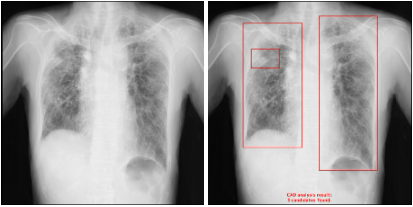

【画像例】

・右肺に無気肺がある症例

・間質性陰影が広がっている症例